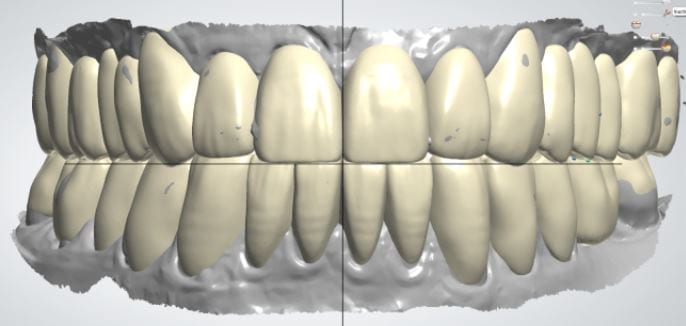

The digital models were then imported into a third party software where a library of tooth morphologies are available for the clinician to choose from.

Once the appropriate library is chosen, the digital wax ups are performed. In the subsequent photos you can see the transparent overlay of the wax-ups to the original position of the existing dentition

Once the case is designed to the ideal vertical dimension then multiple shells can be fabricated for treatment. The wax up model can be uniformly reduced by .5mmm’s circumferentially and a temporary shell can be designed. Once the teeth are prepared, these shells can be relined and seated onto the preps.

Over the course of a few appointments, the vertical dimension was reduced and the temporaries were adjusted to the patient’s desires. The new upper and lower arch were captured with the Medit i500 and the jaws were related to each other.

This was then imported into exocad where the prepped arches from a few weeks prior were force matched to the new bite

After the upper jaw was related to the temps, the same was done with the lower arch. Great care was taken to make sure the arches were properly related to each other throughout the process

CASE DESIGNS

The case was designed by CADENT BESSA, and the models were printed by Burbank Dental Lab with Carbon Printers. There restorations were milled and cut back and layered by Burbank Dental Lab